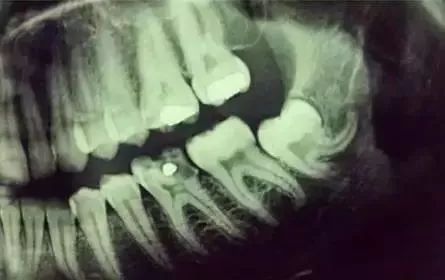

先放几张图,让你们涨涨姿势,不拍片根本不知道你的牙齿长得会有多奇葩!

牙齿的牙根是埋在牙槽骨中的,医生没有透视眼,为了解患牙的牙根的形态、走向、长度及根尖周有无病变及病变大小,或者怀疑有肉眼无法确认的其它牙科问题,都会建议患者去牙科的X光,甚至,口腔CT来全面性地确认问题,以订定合适的治疗计划。